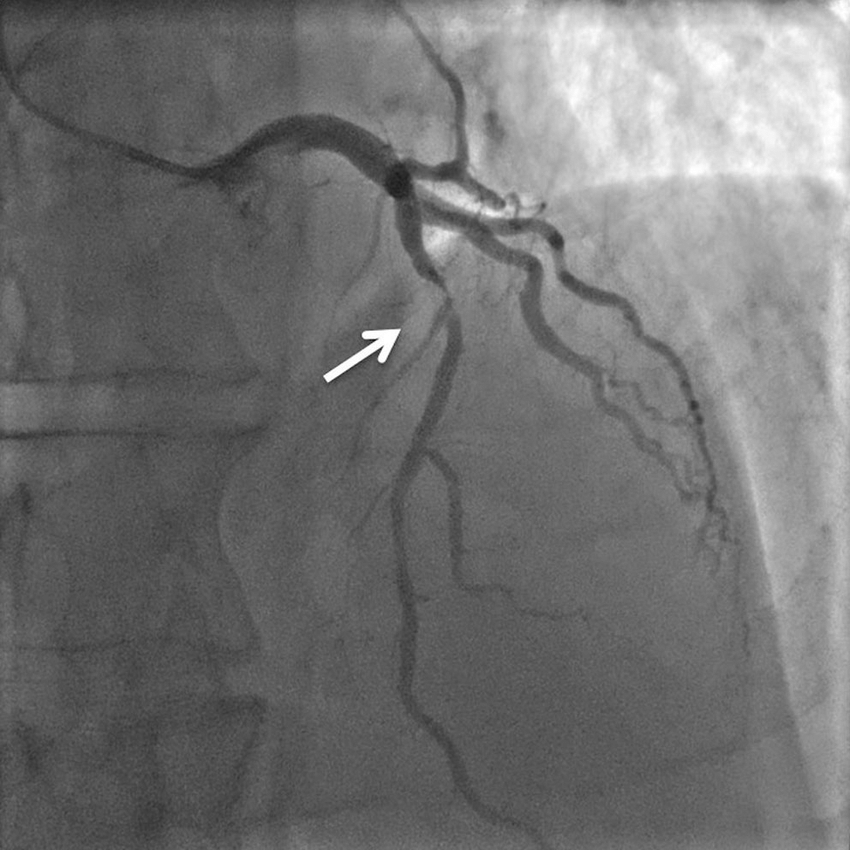

The coronarography is an invasive medical procedure performed on the patient’s coronary arteries.

It is performed by bringing a catheter to the patient’s heart through the radial, femoral, or brachial artery, and injecting contrast dye into the coronary arteries [22].

To control the process the patient is under continuous supervision via coronary angiography imaging (see Fig. 1.1(a)).

The main goal of performing the procedure is an assessment of abnormalities in the patient’s coronary arteries.

The procedure is often paired with the angioplasty treatment in the form of stent implantation in places where the vessel lumen is highly occluded by the atherosclerotic plaques or blood clots (the process of stent implanting is showcased in Fig. 1.1(b)).

Such areas are called stenoses [24] and are the main reason for Coronary Artery Disease (CAD).